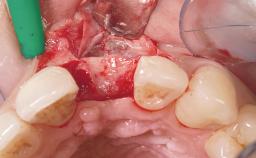

Immediate Flapless Placement of an Implant in a Maxillary Right Lateral Incisor Site

This 43-year-old male patient, a non-smoker, came to our practice because of a fracture of tooth 12 caused by a bicycle accident. Due to the combined para- and infrabony crown and root fracture, tooth extraction, and subsequent implant placement were suggested to the patient as the therapy of choice. The patient had high esthetic expectations with regard to the treatment outcome and asked for an immediate fixed provisional restoration. His individual esthetic risk profile summed up to a medium esthetic risk.

Loading Protocol Immediate

Provisional Implant-Supported Prosthesis Prosthodontic margin > 3 mm apical to mucosal margin Prosthodontic margin > 3 mm apical to mucosal margin

Soft Tissue Contour and Volume Ideal